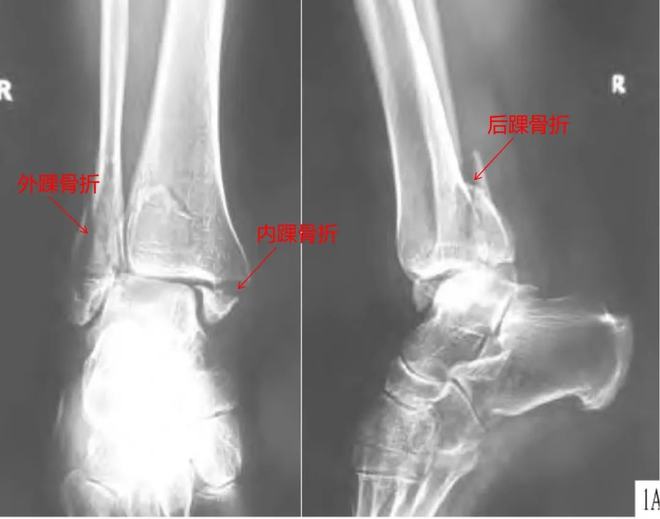

笔者的三踝骨折是踝关节骨折中比较严重的一种类型,三踝骨折除了内外踝骨折外,还合并胫骨远端后踝骨折,是一种严重而复杂的关节内骨折,通常伴有踝关节脱位。对于像笔者这样不能进行急诊手术的三踝骨折合并踝关节脱位患者,通常需要先将脱位复位,石膏固定,待肿胀消退后再进行手术,这样可以有效保留踝关节功能。

三踝骨折X光图丨参考1

踝部骨折手术的最佳时机是什么时候?一般来说,手术的最佳时间是受伤后6小时内,即踝部明显肿胀、水泡出现之前。此时紧急手术切开、复位、固定骨折,可减少血肿,利于切口一期缝合,从而减少患者痛苦,缩短住院时间。